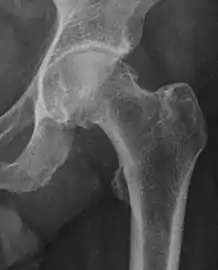

X-ray

Projectional radiography ("X-ray")is often considered first line for FAI.[10] Anterior-posterior pelvis and a lateral image of the hip in question should be attained.[10] A 45-degree Dunn view is also recommended.[10][19]